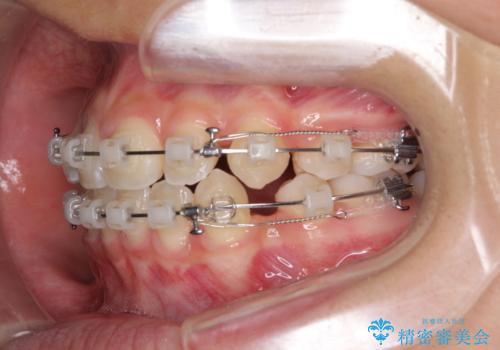

- クリアブラケット

- 2年4ヶ月

当初は八重歯やデコボコが一番気になっていましたが、抜歯矯正により口元の突出感が改善されるにつれ、口の閉じやすさを実感するようになってきました。

部活動で調整来院に来られないことがしばしばあり、期間は予定よりもかかりましたが、きれいに仕上げることができました。